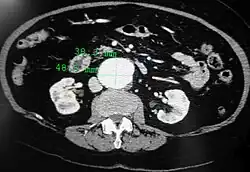

An axial contrast-enhanced CT scan demonstrating an abdominal aortic aneurysm of 4.8 by 3.8 cm -